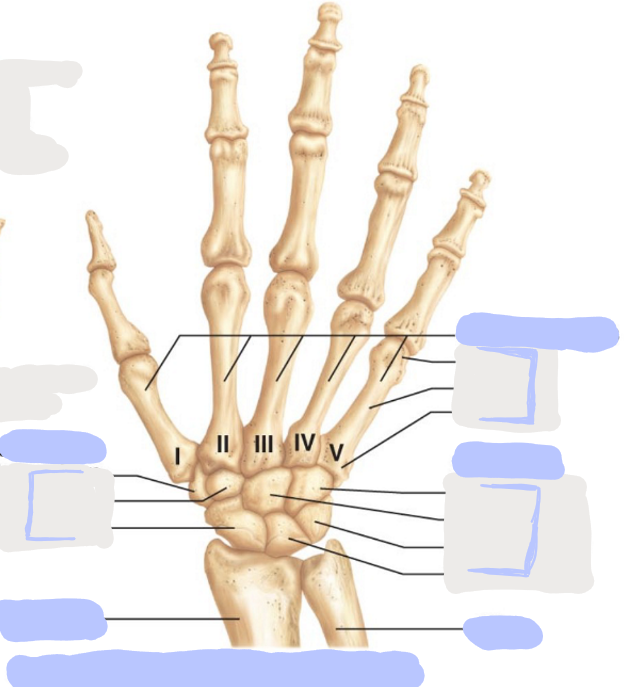

What is this picture of?

Posterior View of the Right Hand

What is here?

Where is the Ulna?

What is here?

Where is the Radius?

What is here?

Where are the Metacarpals?

What is here?

Where are some of the Carpals?

What is here?

Where are some of the Carpals?

How many carpals are there?

8

How many metacarpals are there?

5

How many phalanges are there?

14